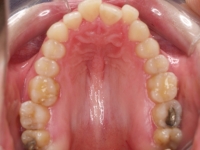

Radiografía de final de tratamiento